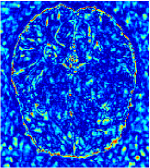

Qualitative comparison between conventional and Meta-learning methods are shown in Figure 1 and 3, which display the reconstructed MR images of the same slice for T1 and T2 respectively, we label the zoomed-in details of HGG in the red boxes. We observe the evidence that conventional learning is more blurry and lost sharp edges, especially in lower CS ratios. From the point-wise error map, we find meta-learning has the ability to reduce noises especially in some detailed and complicated regions comparing to conventional learning.

In general supervised learning, training data need to be in the same or similar distribution, heterogeneous data exhibits different structure variations of features which hinders CNNs to extract features efficiently. In our experiments, raw measurements sampled from different ratios of compressed sensing display different levels of incompleteness, these undersampled measurements do not fall in the same distribution but they are related. Different sampling masks are shown at the bottom of Figure 1 and 2 may have complemented sampled points, in the sense that some of the points which sampling ratio mask does not sample have been captured by other masks. In our experiment, different sampling masks provide their own information from their sampled points so that four reconstruction tasks help each other to achieve an efficient performance. Therefore, it explains the reason that Meta-learning is still superior to conventional learning when the sampling ratio is large.